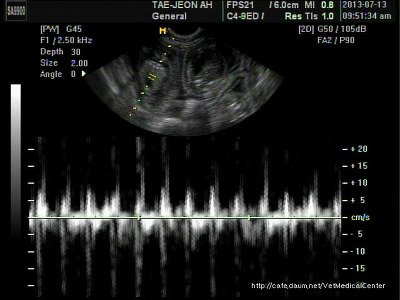

여름이 초음파사진 꼬물이들

사실 아직도 잘모르겠음 걍 동그란게 새끼라니까 아 그렇구나 ㅋㅋㅋㅋ 심장뛰는소리도 들려줬었는데 내심장도 콩닥콩닥 너무 신기하고 여름이가 기특하고 대견한...ㅋㅋㅋ 마치 딸아이가 애기를 가졌다는 소릴 들은마냥ㅋㅋㅋ